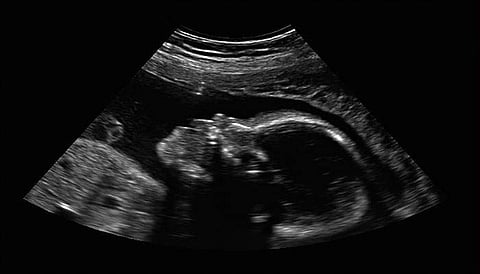

7 സെന്റീമീറ്റര് നീളമുള്ള 150 ഗ്രാം ഭാരമുള്ള കുഞ്ഞിനെയാണ് സഹോദരന്റെ വയറിനുള്ളില് നിന്നും ഡോക്ടര്മാര് ശസത്രക്രീയയിലൂടെ പുറത്തെടുത്തത്. യുവതിയെ സ്കാനിങ്ങിന് വിധേയമാക്കിയപ്പോള് തന്നെ കുഞ്ഞിന്റെ വയറിനുള്ളിലാണ് മറ്റൊരു കുഞ്ഞ് വളരുന്നതെന്ന് ഡോക്ടര്മാര്ക്ക് വ്യക്തമായിരുന്നു.

കുഞ്ഞ് ജനിച്ചതിന് ശേഷം 9 ദിവസങ്ങള് പിന്നിട്ടപ്പോള് നടത്തിയ സ്കാനിങ്ങില്

കുഞ്ഞിന്റെ ഉള്ളില് മറ്റൊരു കുഞ്ഞ് വളരുന്നുണ്ടെന്ന് കണ്ടെത്തി. തലച്ചോറ് ഉള്പ്പെടെ രൂപപ്പെട്ടുവരുന്ന തലയുടെ ഭാഗവും, കാലിലെ എല്ലുകളും ഉണ്ടായിരുന്നതായി ഡോക്ടര്മാര് പറയുന്നു. എന്നാല് കുഞ്ഞിന്റെ തലയോട്ടി രൂപപ്പെട്ടിട്ടുണ്ടായിരുന്നില്ല.